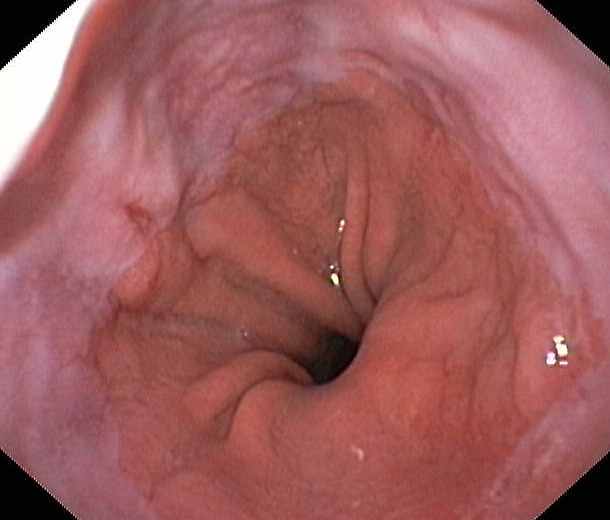

Reflux oesophagitis grade C-D according to the Los Angeles classification